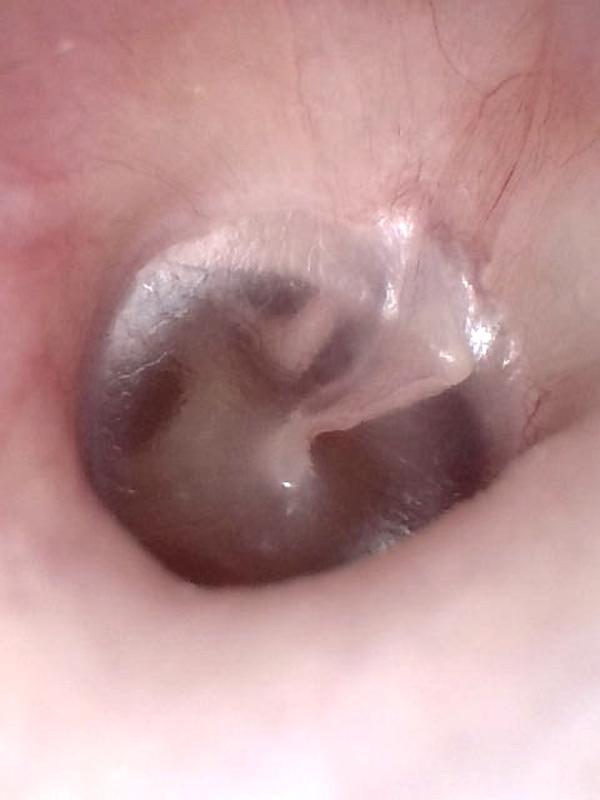

Hemotympanum

Normal Tympanic Membrane